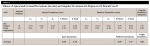

Using the superimposition of the pre- and postoperative CT scans, the positions of the 10 zygomatic implants were evaluated. The results of this evaluation are reported in Table 1 and Table 2. Because two different types of software were used with two different procedures to analyze the results, two separate tables are provided to report an overall statistical calculation of the results.

The following average values were obtained: In "Table 1, Values of Apical and Coronal Deviations…"the apical deviations were recorded as 2.11 mm; the coronal deviations were recorded as 3.55 mm; and the angular deviations were 4.55 degrees. In Table 2, the values recorded were as follows: apical deviations, 2.99 mm; coronal deviations, 2.96 mm; angular deviations, 1.88 degrees. Thus, deviations from the computerized/simulated project were between 2 mm and 3 mm, and angular deviations were between 1.88 and 4.55 degrees.

These values are not directly comparable with those reported studies of accuracy relative to standard implants29-32 for various reasons. The zygomatic implants are inserted freehand and not through a surgical guide, and thus are characterized as "template-assisted" and not "full template guidance."33,34 The length of the drills and zygomatic implants are three to five times greater than standard implants. The training or replica implants always have the same length. Furthermore, contrary to what happens with standard implants, zygomatic implants purposely "perforate" the zygomatic bone at the exit point and the final position of the implants is determined and based on the torque and orientation of the prosthetic connection. Therefore, the values in relation to length cannot be considered in the evaluation of accuracy. In studies of guided surgery, the vertical deviations are also always considered (√ x2s + y2s + z2s) though they cannot be compared with the aforementioned deviations; only the planar of the zygomatic implants, which is not considered a vertical component of the deviation, may be compared (√ x2s + y2s). Therefore, in Table 1 and Table 2 only the x and y values should be considered.